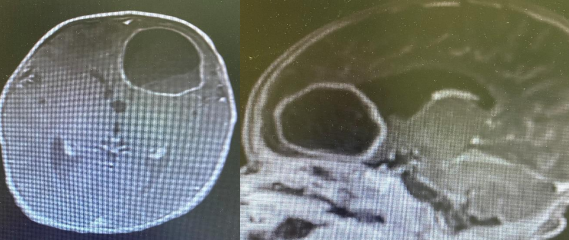

CT /and Magnetic resonance imaging (MRI) brain with contrast was subsequently performed which showed hypo-dense lesion with peripheral enhancement suggestive of intra-parenchymal abscess in left frontal

Figure 1 ?. Head CT: showed a large left frontal hypodense cystic like lesion about 3.5x3.5 cm with density about (13 hu) causing compression of the left lateral ventricle anterior horn with midline shift to the right anteriorly about 3-4 mm with surrounding minimal oedematose changes in both frontal lobes

Figure 2: MRI brain images: There is left frontal intra axial complex cystic  lesion 3.5x3.7x3.9 & thin smooth rim of peripheral enhancement ,internal thin enhancing septation fluid-fluid level and debris causing mass  effect on adjacent  frontal horn with mild midline shift 3mm to the right ,no direct connection seen with the left frontal horn